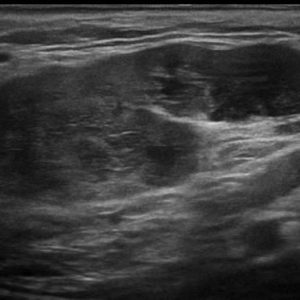

U tuyến nước bọt

Lượt xem: 138» 19-01-2021 -

U tuyến nước bọt

Lượt xem: 153» 19-01-2021 -

U tuyến nước bọt

Lượt xem: 131» 19-01-2021 -

U tuyến nước bọt

Lượt xem: 102» 19-01-2021 -

U tuyến nước bọt

Lượt xem: 146» 19-01-2021 -